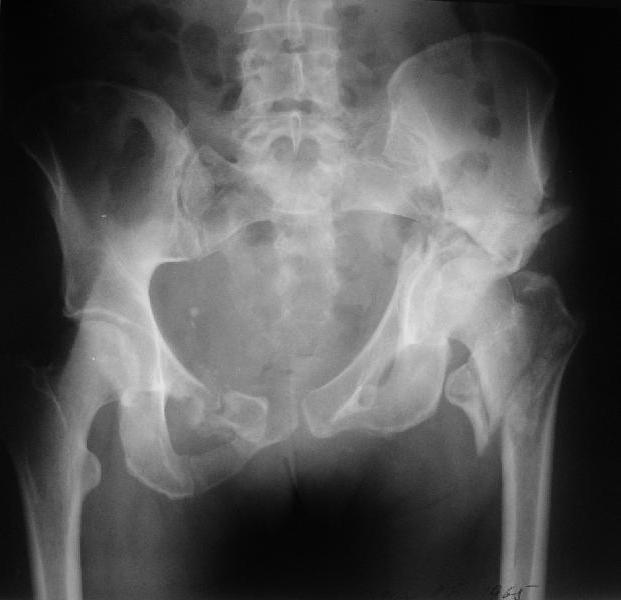

Больная 43 года (промышленный альпинист), 28.07.08 в результате падения с 5 этажа получила политравму: Перелом свода и основания черепа. Вертикально-нестабильное повреждение таза, осложнённое разрывом мочевого пузыря. Чрезвертельный перелом левого бедра. Перелом правой таранной кости, переломовывих правой кубовидной кости. Тупая травма живота, разрыв печени, ушиб почек. Забрюшинная гематома. В день травмы - лапаротомия, ушивание ран печени. Разрыв мочевого пузыря не диагностирован. Течение болезни осложнилось развитием мочевого затёка и обширной пред- и забрюшинной флегмоны, сформировался свищ мочевого пузыря. 19.8.2008 вскрытие, дренировние флегмоны, ревизия мочевого пузыря, обтурация мочевого свища (свищ закрылся в октябре), 1.10.2008 некрэктомия, пластика по Шеде-Лидскому правой кубовидной кости. По результатам КТ диагностирован рак правой почки (диагностическая находка), 8.10.2008 нефрэктомия справа. Переломы велись консервативно. Имеется вертикальное смещение левой половины таза с выраженным отведением крыла (клинически подвижности нет), несросшийся низкий двухколонный перелом левой вертлужной впадины с потерей конгруэнтности, укорочение около5 см, застарелый разрыв лонного сочленения, неправильно сросшиеся переломы обеих ветвей правой лонной кости с укорочением, патологическая подвижность лоно-седалищного фрагмента слева. Правая нижняя конечность неопорна, несмотря на то, что лежа прямую ногу поднимает, ходит на левой ноге (ортопедическая обувь) с костылями, справа тазобедренный ортез. Седалищные нервы работают.Урологи отпустили больную на 6 мес.

Извиняюсь, ошибся : опорная нога у больной правая. Левая нога неопорная, т.к. сращения на уровне бедра и вертлужной впадины нет.